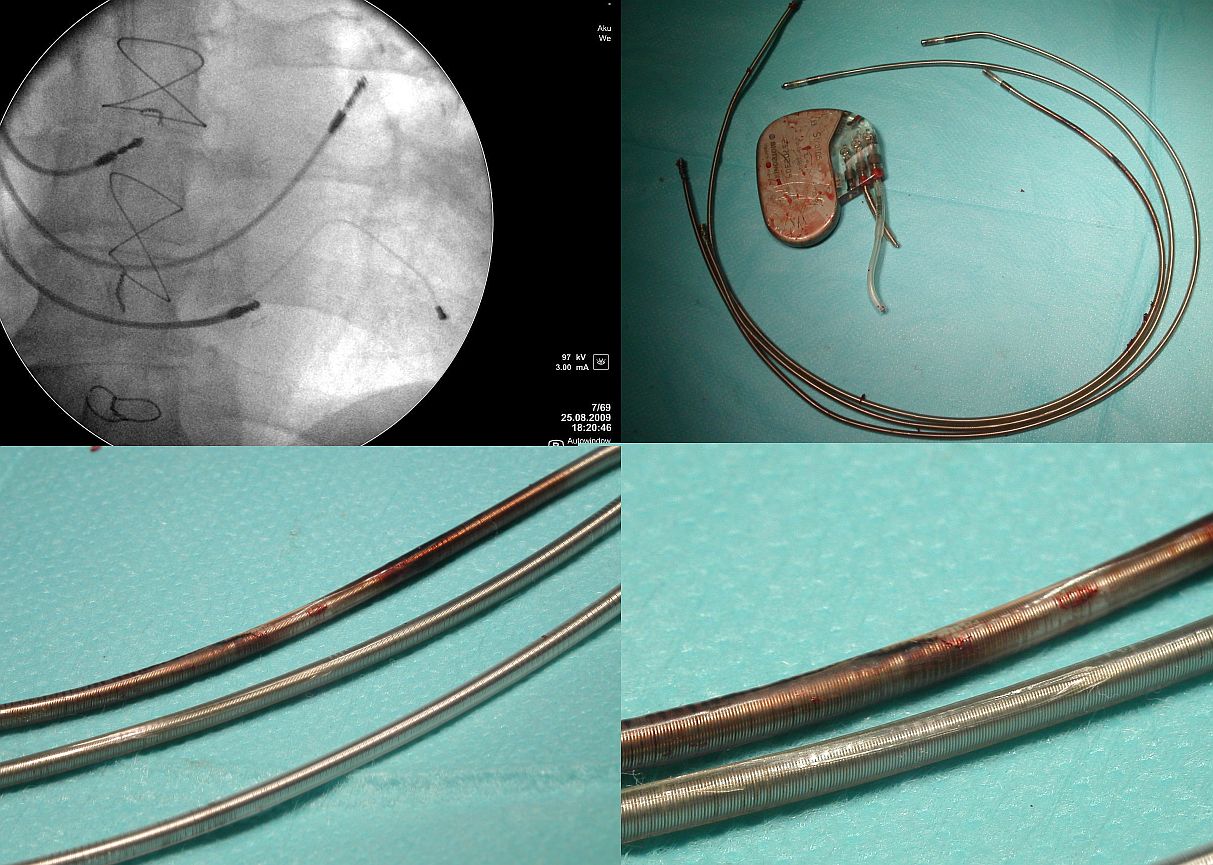

- Występowanie zjawiska. Opisane w piśmie

przetarcia dotyczą elektrod defibrylatorowych z osłonkami

silikonowymi. Osłonki silikonowe stosowane były od 40

lat przez wszystkie firmy produkujące elektrody do stałej

stymulacji serca i w rzeczywistości podatność na

przetarcie nie jest charakterystyczną wadą elektrod tej

jednej firmy. Przetarcia elektrod dotyczą bowiem produktów

WSZYSTKICH firm, których elektrody posiadają osłonkę

silikonową. Wg naszych wieloletnich badań, zjawisko

przetarcia osłonki silikonowej z odsłonięciem spirali

(czyli perforacją osłonki zewnętrznej) obserwuje się u

ok. 25% pacjentów, u których usunięto elektrody z różnych

przyczyn (50% to wskazania infekcyjne). I co ważniejsze -

jak wskazują nasze obserwacje - w ogromnej większości

przetarcia osłonek elektrod są bezobjawowe (!!!). Skala

zjawiska jest nieznana, na pewno większa niż mogło by

się wydawać.

- Okoliczności występowania. Każdy, kto wymienia

stymulatory widział przetarcie elektrody o obudowę

stymulatora. Większość z nas widziała również

przetarcie elektrody o dolny brzeg obojczyka. Tym

zjawiskom można starać się zapobiec poprzez poprawę

techniki zabiegu implantacji. Identyczne pod względem

morfologicznym przetarcia występują w układzie żylnym,

a przede wszystkim w obrębie prawego serca. Niezależnymi

czynnikami zwiększającymi prawdopodobieństwo wystąpienia

przetarcia są: wiek i liczba elektrod w układzie

sercowo-naczyniowym, obecność w układzie elektrody

wchodzącej do zatoki wieńcowej oraz obecność zbędnych

nieprawidłowych pętli w prawym przedsionku bądź prawej

komorze. Czyli czas i wzajemny kontakt poruszających się

w różnych kierunkach elektrod mają znaczenie decydujące.